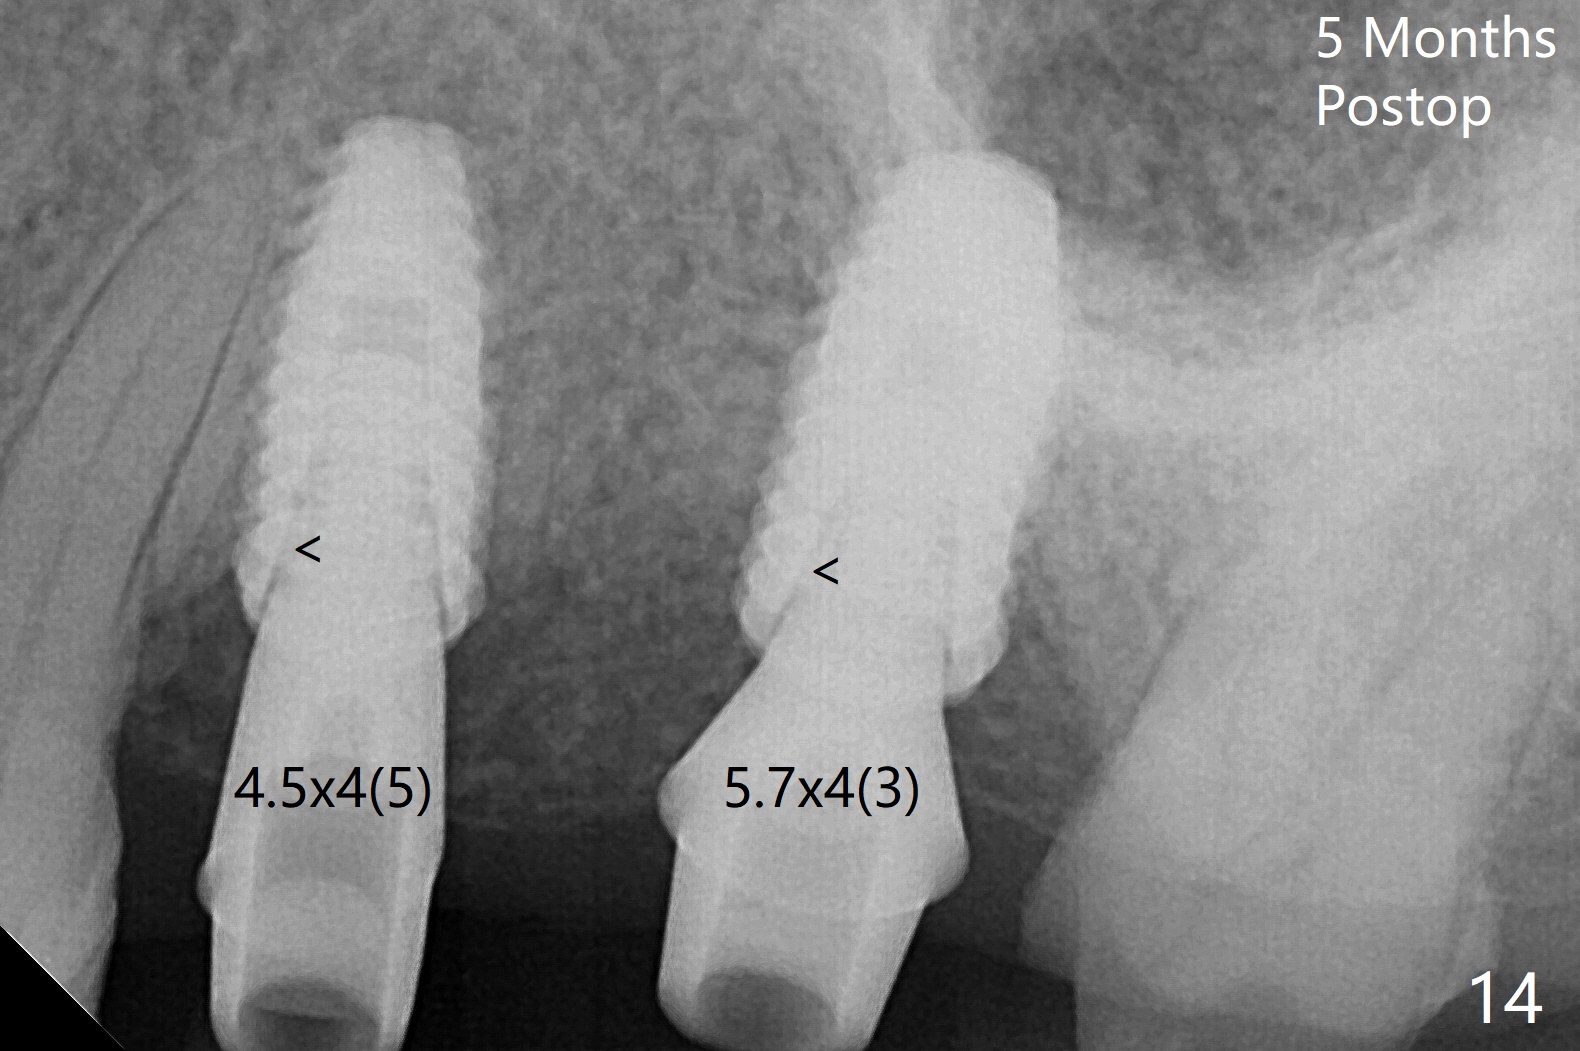

After extraction of the tooth #13 residual root, the bone in the distal wall of the socket looks white. Intraop PA rules out root structure (Fig.1 *). Osteotomy is conducted according to drill sequence. Bitewings are taken to check implant placement level (Fig.2,3). Following implant level adjustment and healing abutment installment (Fig.4,5 (*: bone graft)), the implant at #13 is found to be close the root of #12 (Fig.6 *), i.e., not parallel to the implant at #14. Introspectively, 2.2x10 mm drill seems to be long. When it touches the bone, the cylinder portion of the drill (Fig.7 red) does not engage into the sleeve (green). When it goes into the bone, it may have been deflected mesial due to the slope of the distal wall of the socket (hard bone, Fig.8 open arrow)). If a shorter drill (such as 2.2x7.3 or 8.5 mm) were used (Fig.9), the deflection would be minimal if drilling is slow (Fig.10). CT taken 1 week postop shows that the implant at #13 is approximately 1 mm near the root of the tooth #12, but the neurovascular bundle to the latter seems not to have been interrupted (Fig.11,12). The buccopalatal trajectory at #14 is within normal limit (Fig.11,13 (B: buccal)). There is no periapical radiolucency at #12 five months postop (Fig.14). However the cemented abutments are incompletely seated (<). The patient is reluctant to return for impression 17 months postop (due to coronavirus); with attention, the same abutment at #13 is reseated completely; an abutment with longer cuff and narrower diameter is also seated completely (Fig.15).